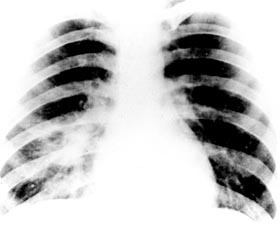

Khởi bệnh của thể phổi thường điển hình đi kèm bởi sốt cao, nhức đầu, chán ăn và đau mỏi cơ toàn thân. Đau ngực là hay gặp, nhưng có ho hoặc không ho có đờm là một dấu chỉ điểm có giá trị (hallmark) của thể này. Tổn thương khoang cũng có thể nhìn thấy trên phim chup X quang phổi tương tự như hình ảnh trong lao phổi.